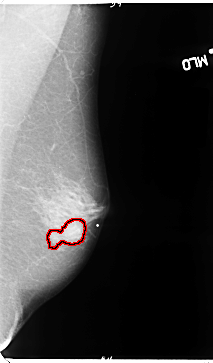

FILE: B_3088_1.LEFT_MLO.OVERLAY

TOTAL_ABNORMALITIES 1

ABNORMALITY 1

LESION_TYPE MASS SHAPE LOBULATED MARGINS OBSCURED-ILL_DEFINED

ASSESSMENT 3

SUBTLETY 3

PATHOLOGY MALIGNANT

TOTAL_OUTLINES 1

BOUNDARY